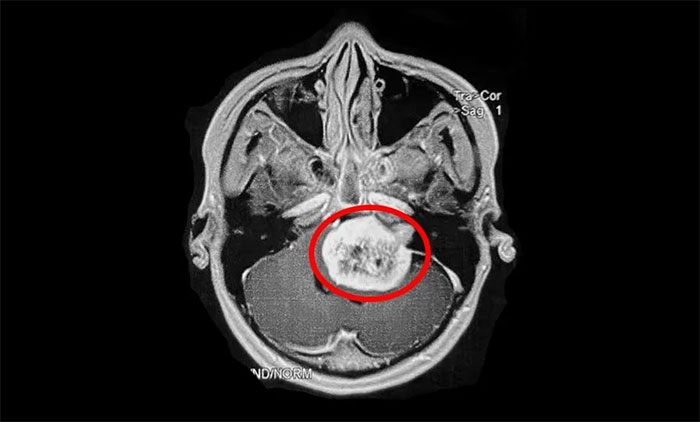

值得注意的是,聽(tīng)神經(jīng)瘤早期表現(xiàn)易與耳聾及其他一些顱腦腫瘤混淆,出現(xiàn)相應(yīng)癥狀時(shí),患者應(yīng)及早到具備專(zhuān)科診療能力的醫(yī)療機(jī)構(gòu),通過(guò)聽(tīng)力學(xué)檢查、面神經(jīng)功能檢查、前庭功能檢查、影像學(xué)檢查(聽(tīng)神經(jīng)瘤主要檢查手段),即可明確診斷。

▲ 影像學(xué)檢查是聽(tīng)神經(jīng)瘤主要檢查手段(示意圖)